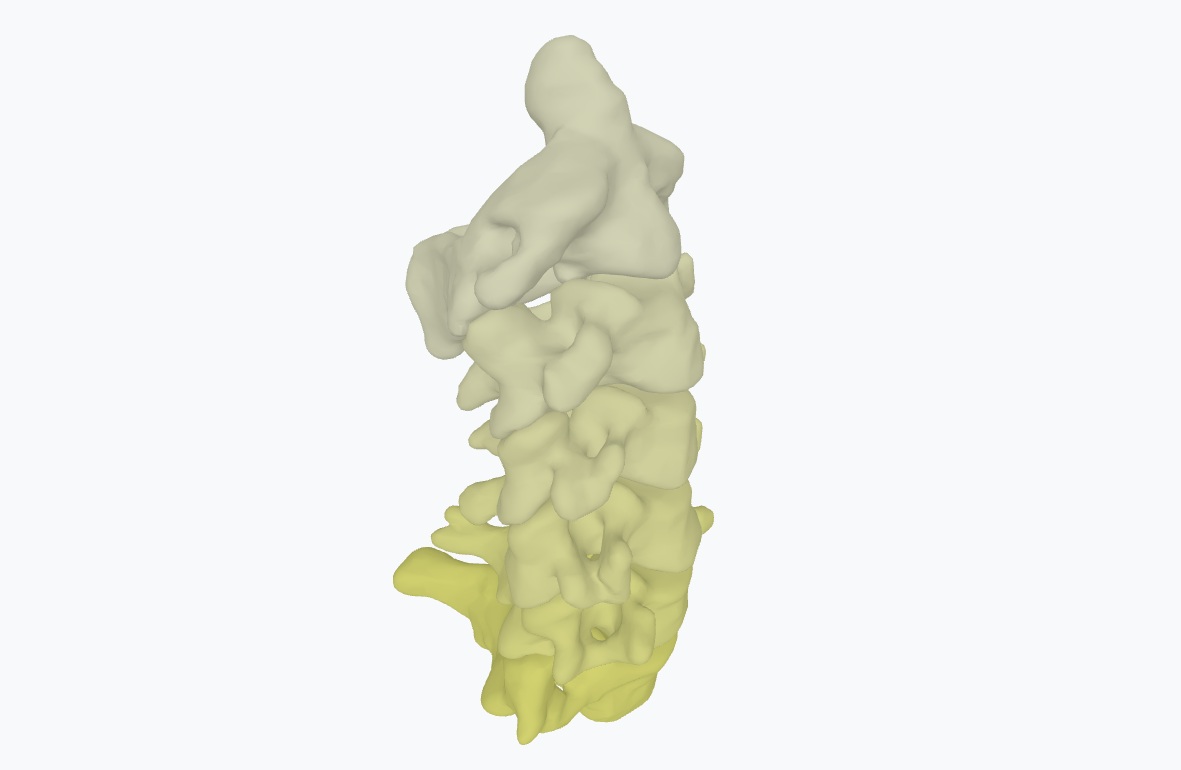

Metástasis en hígado

Planificación de hepatectomía para caso de tumor neuroendocrino de la primera porción del duodeno con metástasis hepáticas.

Metástasis en hígado

Planificación de hepatectomía para caso de tumor neuroendocrino de la primera porción del duodeno con metástasis hepáticas.